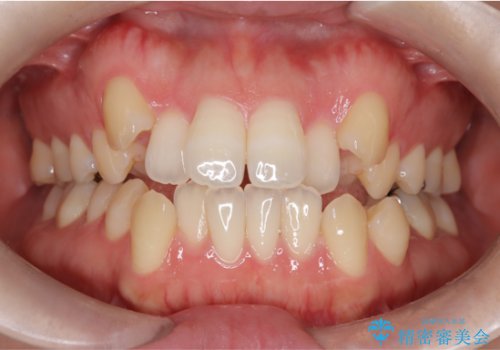

[前歯のねじれ 部分]ワイヤーとマウスピースの併用矯正治療

担当医 大元洋佑

![[前歯のねじれ 部分]ワイヤーとマウスピースの併用矯正治療 の症例 治療前](https://seimitsushinbi.jp/wp/wp-content/uploads/2024/11/IMG_3012-500x350.jpg?v=1731313349)

![[前歯のねじれ 部分]ワイヤーとマウスピースの併用矯正治療 の症例 治療後](https://seimitsushinbi.jp/wp/wp-content/uploads/2024/11/d62ebcf4699c90efb9ffd5ed659b7480-500x350.jpg?v=1731313408)